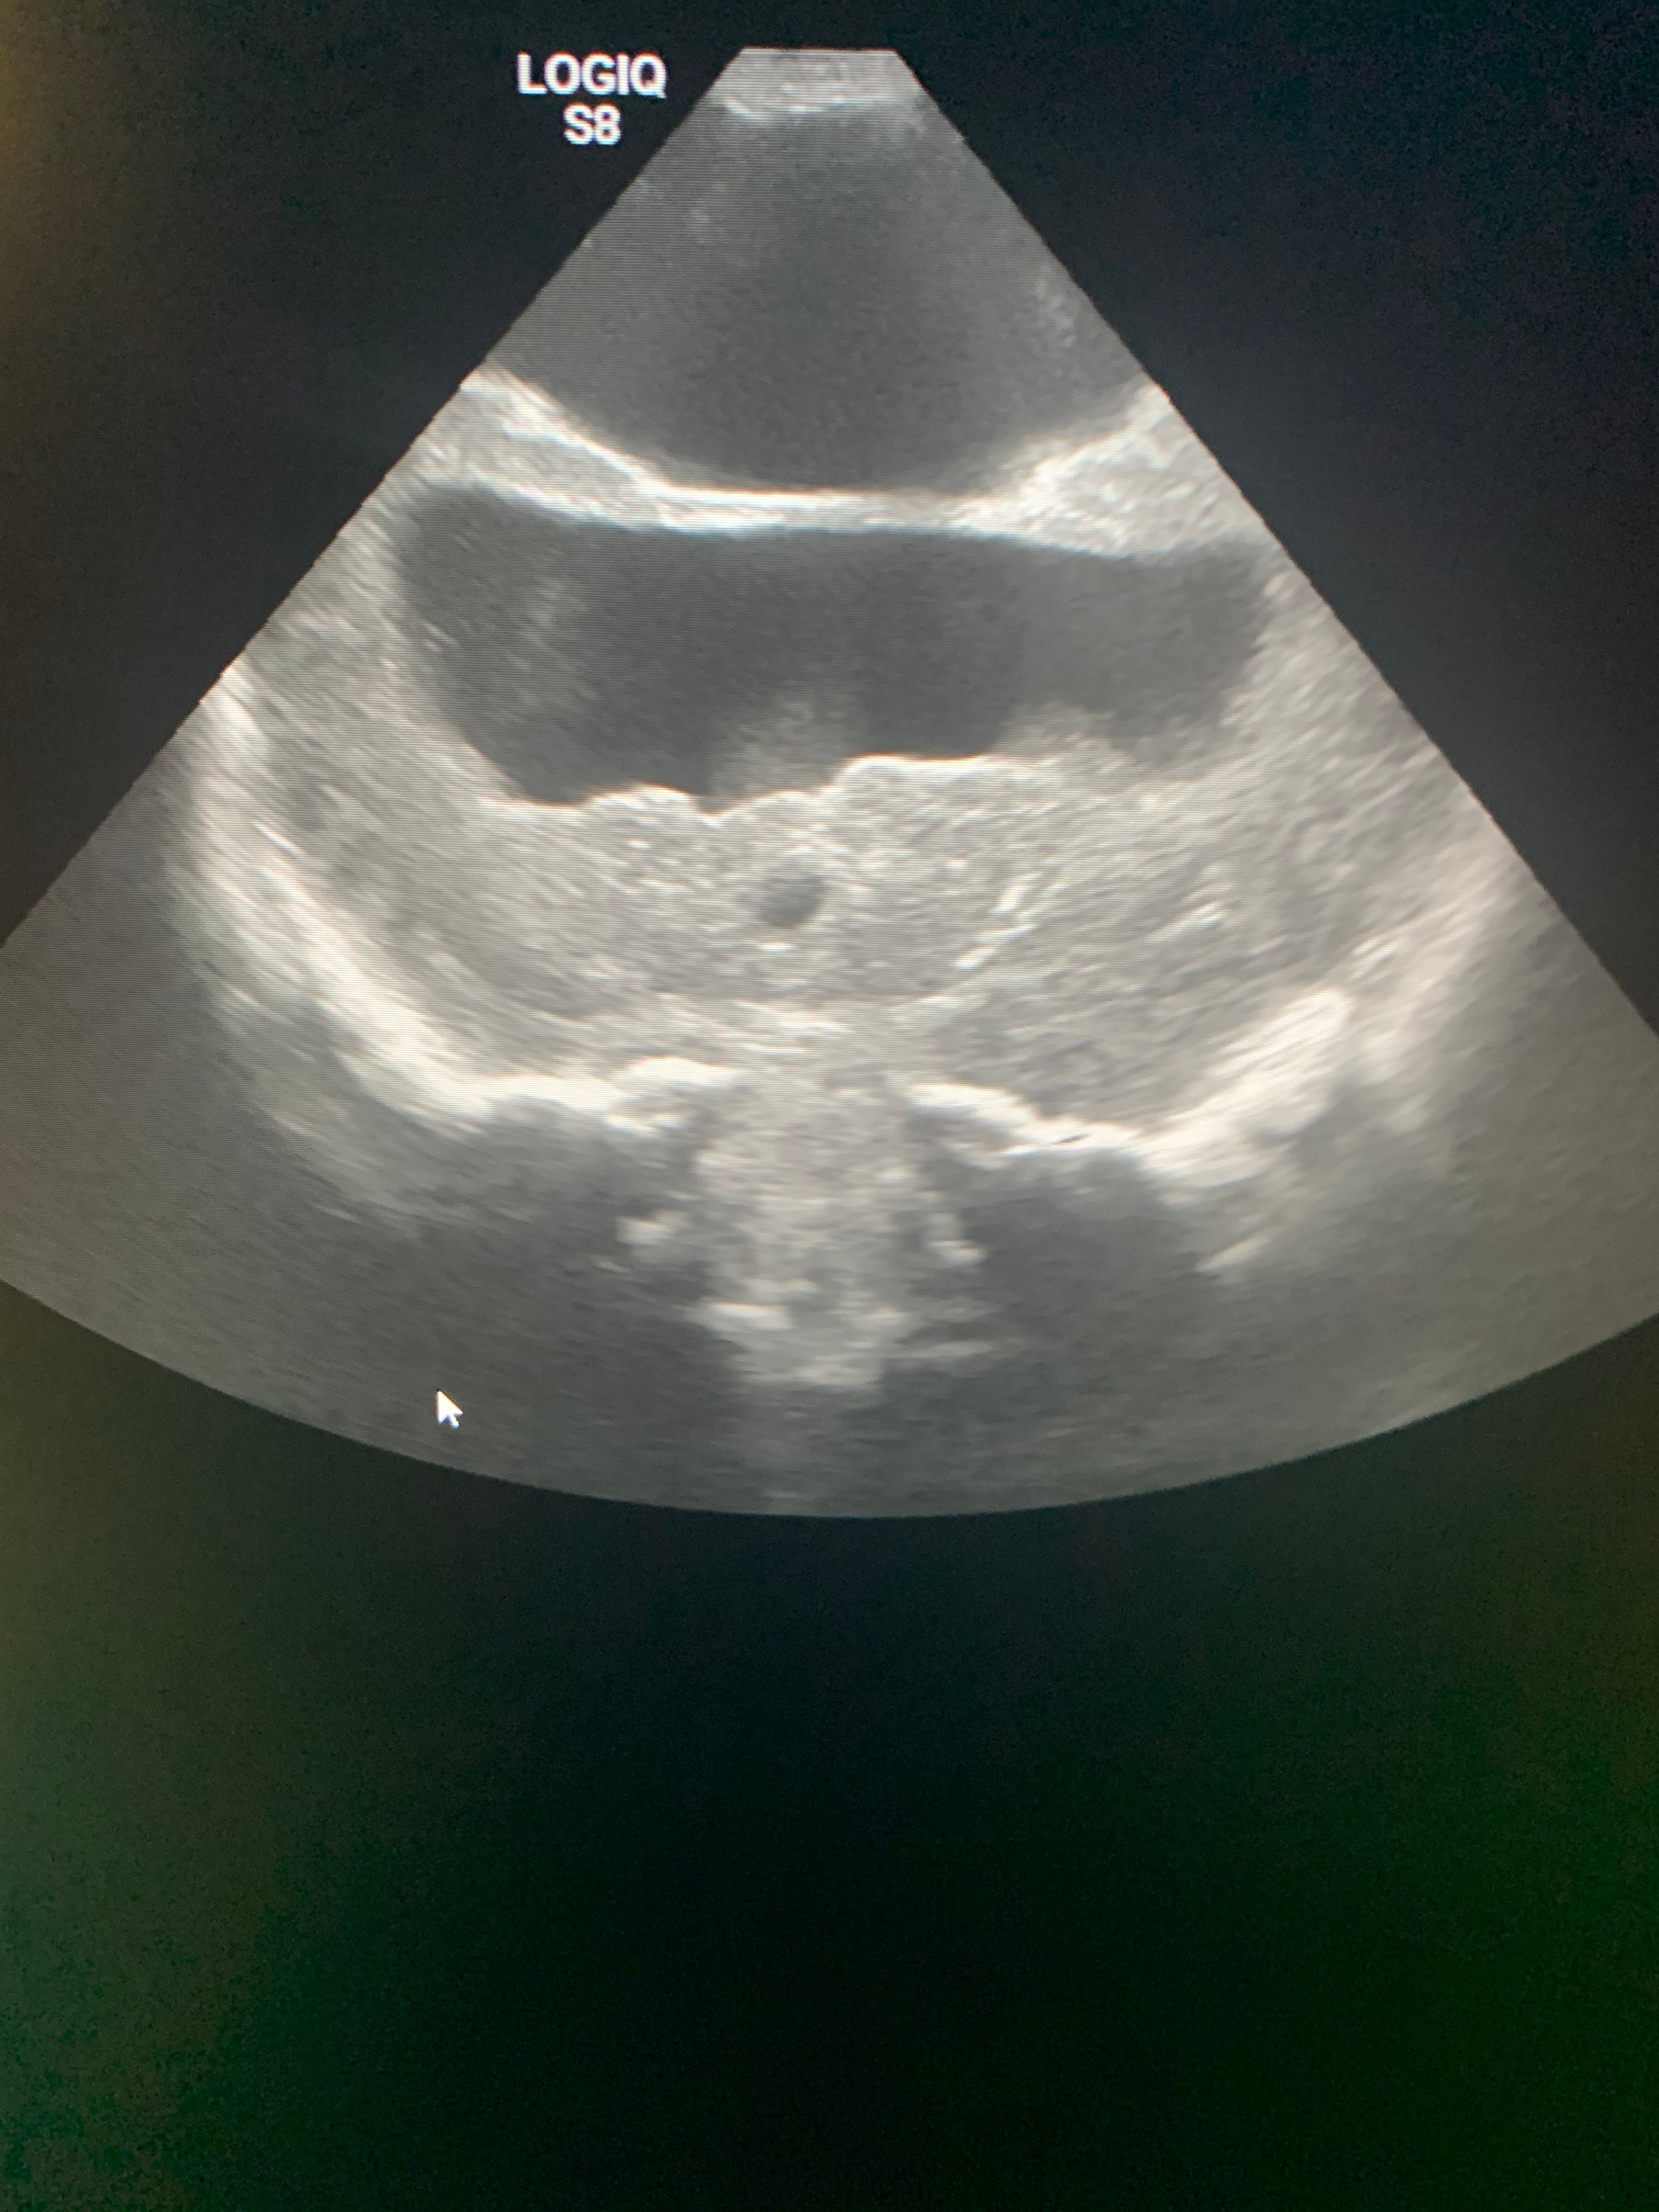

Image IQ Quiz: Infant With Prenatally Diagnosed Abnormality on Ultrasound

40-week-old male with a prenatally diagnosed abnormality on screening ultrasound. What is the diagnosis?

40-week-old male with a prenatally diagnosed abnormality on screening ultrasound. What most likely represents the imaging finding?